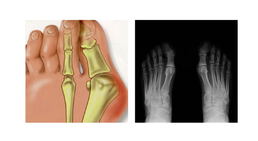

Fußchirurgie

ist eine der häufigsten Fehlbildungen der Zehen. Er entsteht meistens durch das dauerhafte Tragen zu enger oder unbequemer Schuhe. Deshalb leiden...